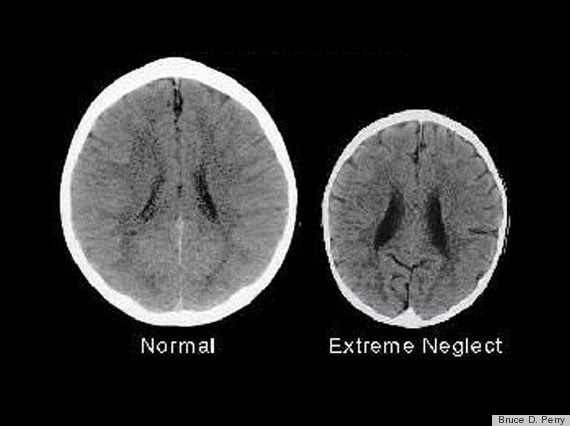

συμβαίνει όταν ένα παιδί κακοποιείται;

Η

ανάπτυξη των παιδιών δεν είναι ολοκληρωμένη

όταν το παιδί δέχεται το τραύμα με

αποτέλεσμα να μην έχει αναπτυχθεί ακόμα

η αναγκαία νοητική και συναισθηματική

του ικανότητα για να κατανοήσει, να

ελέγξει και να το επεξεργαστεί το τραύμα.

Το τραύμα λοιπόν όχι μόνο στιγματίζει

αλλά καθορίζει την ίδια του την ταυτότητα.

Πιο συγκεκριμένα, η ίδια η ανάπτυξη των παιδιών καθυστερεί καθώς όλη η ενέργεια του παιδιού επικεντρώνεται στον αγώνα επιβίωσης. Μέρος αυτού του αγώνα είναι η ανάπτυξη συγκεκριμένων τρόπων αντιμετώπισης της κατάστασής (οι ονομαζόμενες ‘άμυνες’) έτσι ώστε να μπορέσουν να μείνουν όσο γίνεται πιο ασφαλή και να επιβιώσουν μέσα στον σωματικό ή και ψυχικό πόνο στον οποίο είναι καταδικασμένα να ζούνε.